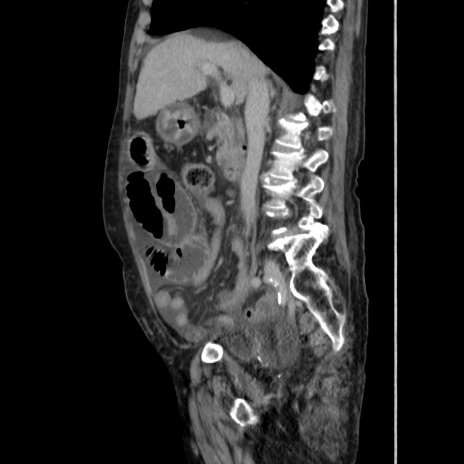

症例31(矢状断像)

【症例】80歳代 女性

【主訴】腹部膨満感

【現病歴】他院にて肝硬変にてフォロー中。1週間前から便秘、腹部膨満感、臍部腫瘤あり受診となる。

【既往歴】肝硬変

【身体所見】腹部膨隆あり、皮膚変化なし、疼痛なし。

【データ】WBC 4600、CRP 0.25